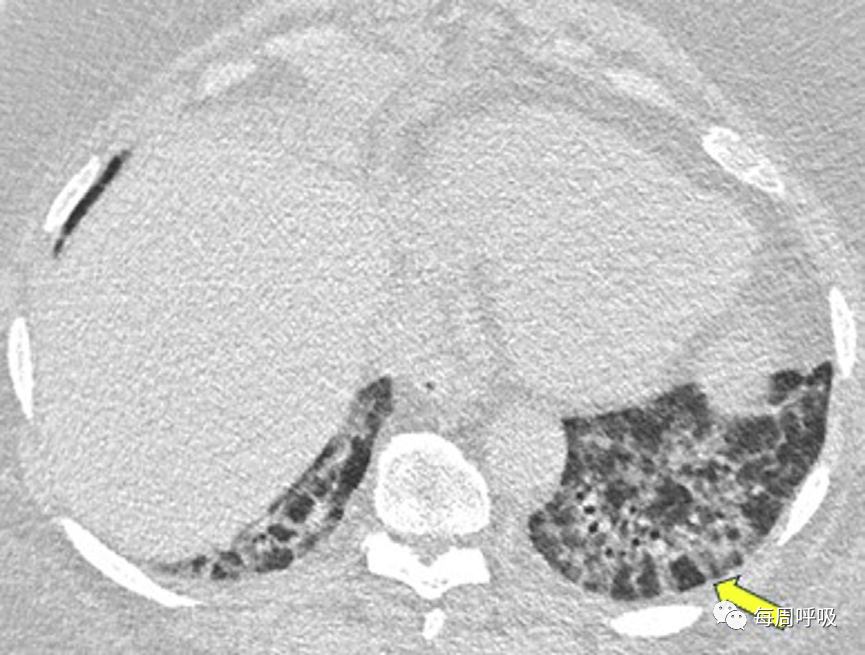

当以线性或网状为主的OP进一步发展,在周围实变或GGO后,基底和胸膜下网状形成,提示间质纤维化的发展(图17)。尽管蜂窝状和结构扭曲的发展可能表明纤维化的进展,OP也可在UIP或IPF中看到,使最终诊断复杂化。此外,OP可导致广泛的双基底牵引性支气管扩张,与背侧胸膜下肺区相对保留相关,其结果与非特异性间质性肺炎(NSIP)相似,并经常重叠(图18,图19)。

图19非特异性间质性肺炎(NSIP)。我们对一名病态肥胖且进行性呼吸困难的67岁男性进行了轴位CT扫描。肺基底部CT显示周围支气管壁增厚,伴有边界不清的磨玻璃密度和小叶周围增厚,特别是在左基底部(箭头),这些表现提示NSIP。外科肺活检结果与机化性肺炎相符。